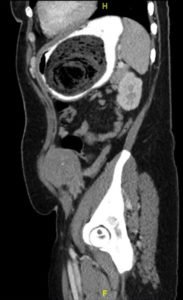

Computed tomography (CT) of the abdomen and pelvis with oral and intravenous contrast was ordered to evaluate her symptoms. The CT showed three large collections of ingested material seen as hypodense material with circular rings surrounded by the hyperdense oral contrast (see red outlines). These findings are consistent with bezoars, the largest of which measured 11.5 x 7.8 cm. There was also thickening of the gastric wall (see blue outline), most notably at the pylorus, consistent with partial obstruction.